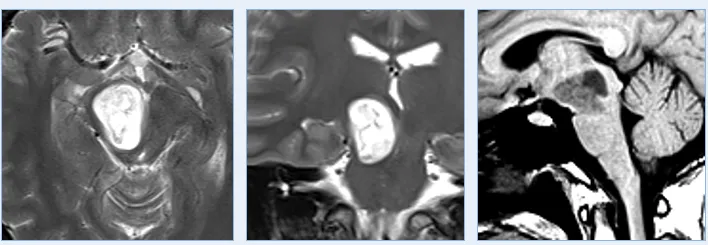

20岁的女孩米亚因剧烈头痛查出一个背侧外生的中脑肿瘤引起梗阻性脑积水。瘤子位置确实深,而且累及中脑和上脑桥。手术中稍不注意,或者损伤中脑患者变成植物人,损伤桥脑引起半身瘫痪,严重损伤延髓影响呼吸功能。

由于肿瘤与周围的脑干实质有很好的边界,巴教授术中肿瘤全切,术后MRI复查明确未见肿瘤残余。术后11年随访时:术后MRI显示患者没有肿瘤残留或复发。患者的临床状况良好,眼球运动正常。随访至今,她为自己赢得了19年无复发,状况非常好。

图:术前术后脑磁共振对比,脑干胶质瘤全切,无神经脑组织损伤。